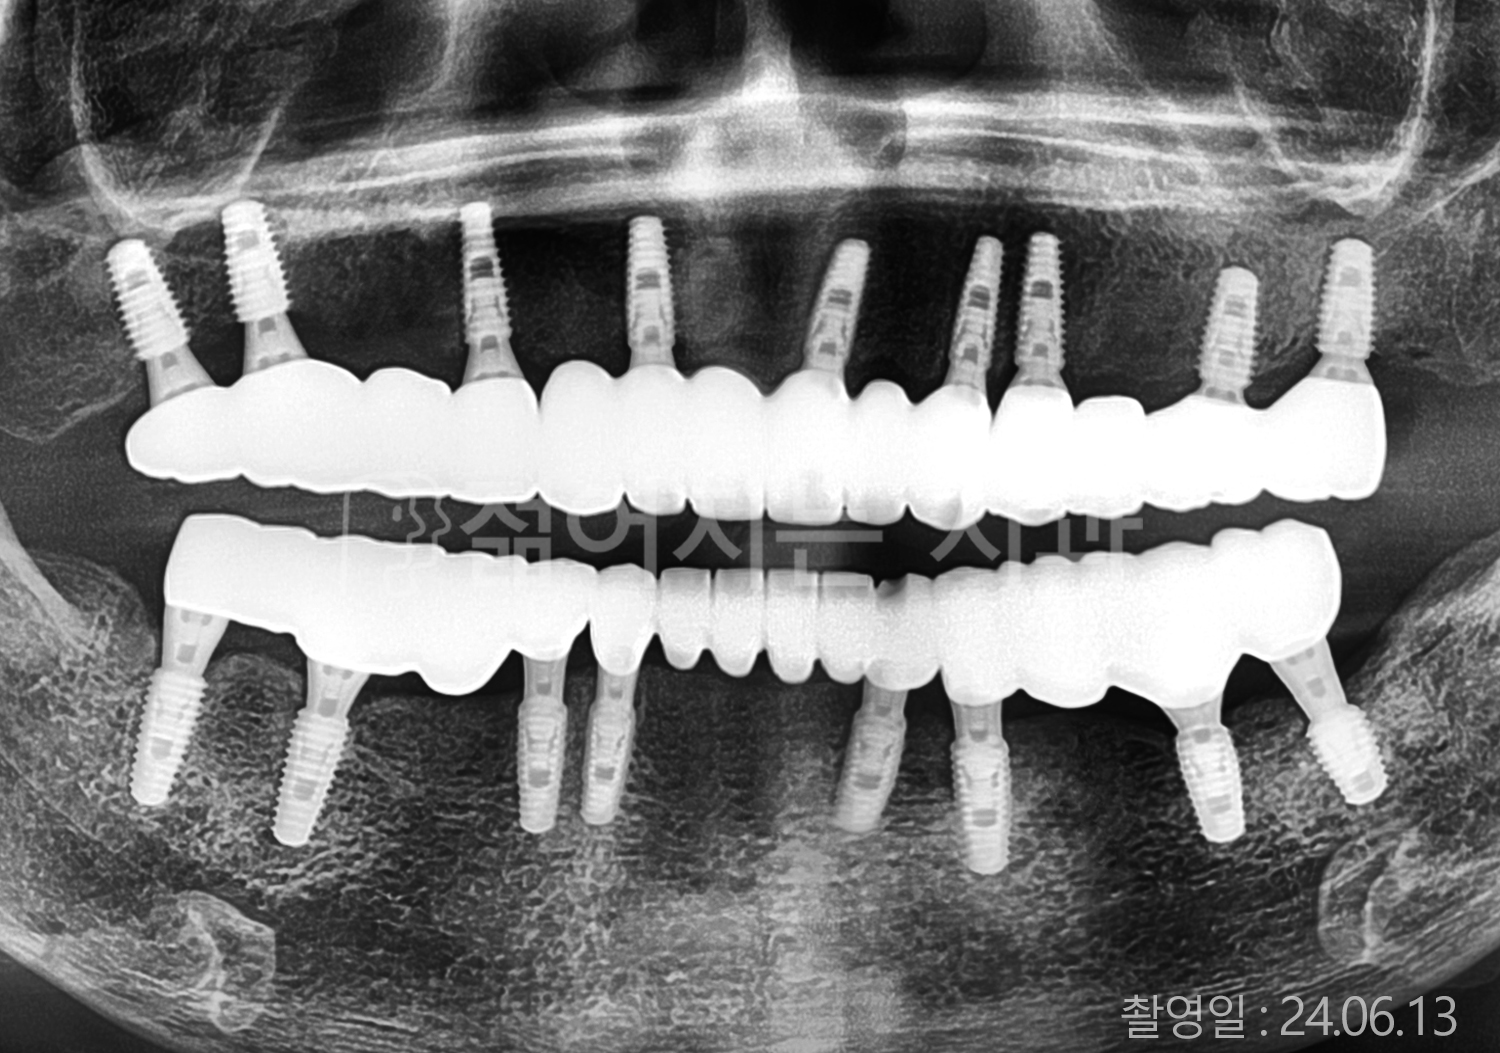

치료사례(치아)

• 70대 고혈압, 고지혈증 전체치아 10개 이상 임플란트

• 60대 당뇨, 간염 전체치아 10개 이상 임플란트

• 80대 골다골증 전체치아 6개 이상 임플란트

• 70대 고혈압, 당뇨 전체치아 10개 이상 임플란트

• 60대 간 질환 전체치아 10개 이상 임플란트

• 60대 전체치아 10개 이상 임플란트

• 70대 전체치아 10개 이상 임플란트

• 50대 전체치아 10개 이상 임플란트

• 60대 고혈압, 고지혈증 전체치아 10개 이상 임플란트

• 40대 고지혈증, 뇌혈관 질환 전체치아 10개 이상 임플란트